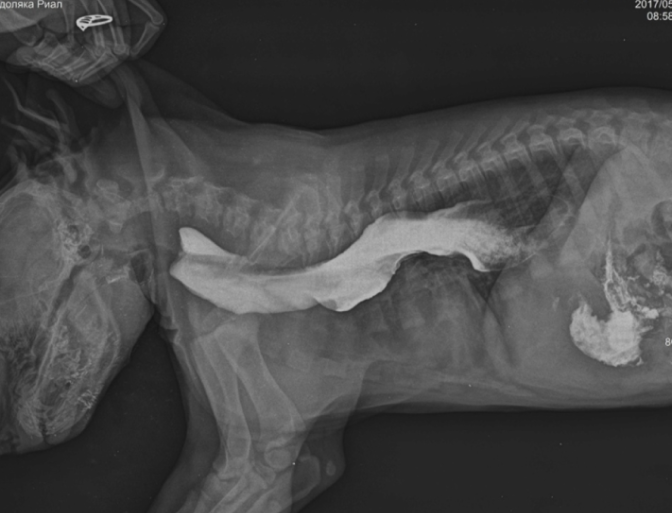

Важно: Мегаэзофагус вызывает именно срыгивание. Если вы видите, что питомец срыгивает непереваренной пищей — это повод для срочной диагностики